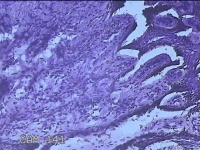

外阴部肿物

性别

女

年龄

34岁

临床诊断

纤维瘤病(外阴部)

一般病史

无

标本名称

大体所见

灰白粉红色组织0.8x0.5x0.2cm一块,表面糜烂。